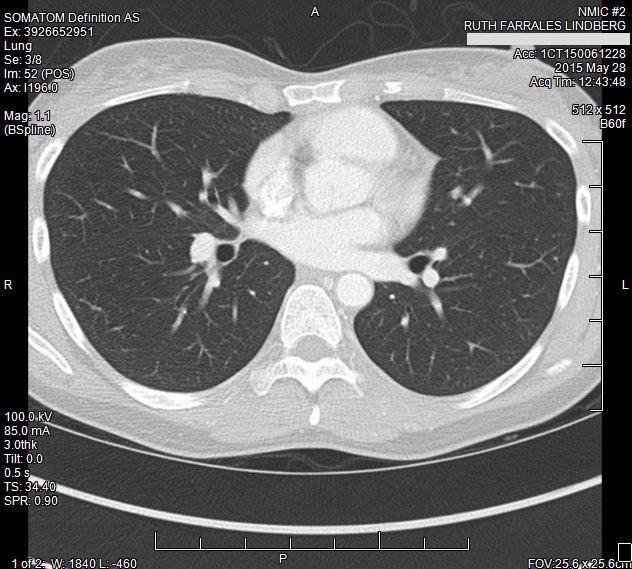

After surgery in November of 2014, I continued to have follow-up CT scans every 3 months. In April of 2015 a CT of my chest showed an enlarged lymph node near my lung. More scans and then a biopsy confirmed our worst nightmare – cancer, again. After nine months of a brutal chemotherapy regimen, and then surgery… this cancer would just not go away. We could not escape.

Meanwhile doctors at two different medical centers had determined that the cancer in this lymph node had features of both the first and second cancers. At long last, a diagnosis was coming into focus – metastatic endometrial cancer that had significant variation within it. There were parts of the tumor that were garden-variety endometrial cancer, and that was what they found when I had surgery in 2014. Then there were other parts of the tumor that were made up of cancer cells that hid their tracks and didn’t follow any rules. Those parts of the tumor were what had metastasized – into my abdomen in 2013, and then again into the lymph node in my lung in 2015. With all this in mind, the treatment my doctors proposed was chemotherapy. I asked my doctors for another CT scan. I did not tell them what had happened and that I believed that God had healed me – I didn’t think they would understand. I didn’t feel, however, that I could refuse chemo without having some visible proof (for both my doctors, and to be honest, myself) that the cancer was gone.

I had another CT scan at the end of May 2015. This was a month and a half after the CT scan which had showed the recurrence. This is a screenshot of the CT which showed the cancerous lymph node:

And this is the CT which showed that God had indeed healed me:

The lymph node is completely back to normal size and appearance. The cancer had completely disappeared.

My doctors could not explain what had happened, but were all in agreement that no treatment was now necessary, since there was nothing there to treat. Since then I have had several follow-up CT scans which have all been completely negative for cancer.